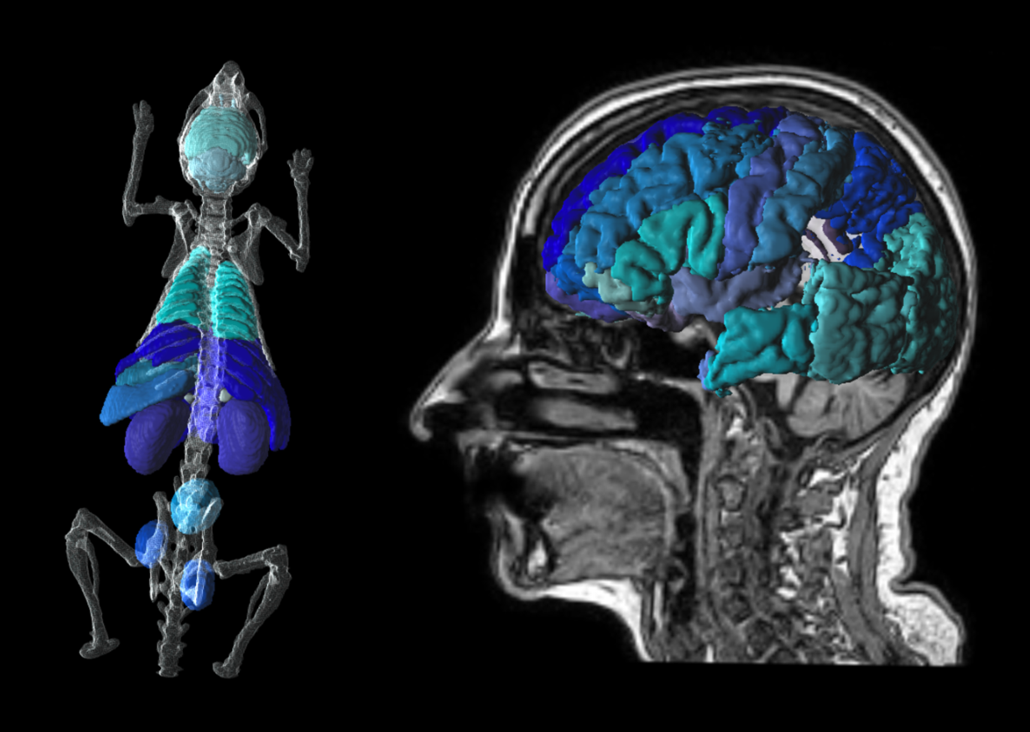

P3D Extended 3D Rendering

Translational tools to go from mouse to man. Easily transform atlases from template to individual space. Create stunning visuals for publication.

PNEURO Human Brain Analysis & Neurology Package

pmod’s PNEURO tool gives you streamlined segmentation for human brain PET and PET/MR and direct access to statistics, kinetic modelling & parametric mapping.

PNROD Rodent Brain Analysis

PNROD gives you brain segmentation workflows for small animal PET, PET/CT and PET/MR with the same direct access to statistics, kinetic modelling & parametric mapping.